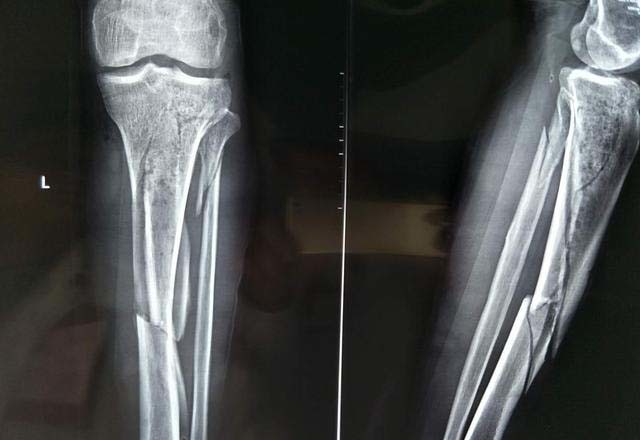

脛骨骨折 症状-脛骨高原骨折の症状 若い人の骨折では交通事故や高所作業中の転落などの高エネルギー外傷によって骨折します。 高齢者では転倒で膝をぶつけたときに骨折することが多いようです。 症状としては ・膝関節運動時の痛み ・荷重時の膝関節の激しい痛み脛骨高原骨折(けいこつこうげんこっせつ)は膝の部分の脛骨の上部が骨折した状態のことである 。 症状は膝の痛み、むくみ、膝の可動域の減少である 。 脛骨高原骨折をした場合、一般的に歩くことができなくなる 。 合併症には動脈血管や神経の損傷、関節炎、コンパートメント症候群などが

回, 脛骨高原骨折に対し観血的治療を行った症 例について, その治療方法と術後成績について 検討したので報告する 対象および方法 対象は脛骨高原骨折に対して観血的治療を施 行した9例9関 節である 受傷時年齢は37~86 歳 (平均565歳) であった足の骨の解剖を図やイラストでわかりやすく解説していきます。 これを読めばどんな名前のどんな形の骨があるのか、きっと理解することができますので、ぜひ最後までお読みください。 足っていろんな骨が集まっています。 あっ、先にい膝の前面を強く打ったような場合、膝関節内で骨折することがあります。 レントゲン写真を撮っても、骨折していることがわからず、打撲であると診断されてしまう場合もあります。 このページでご紹介する後十字靭帯付着部裂離骨折は膝の